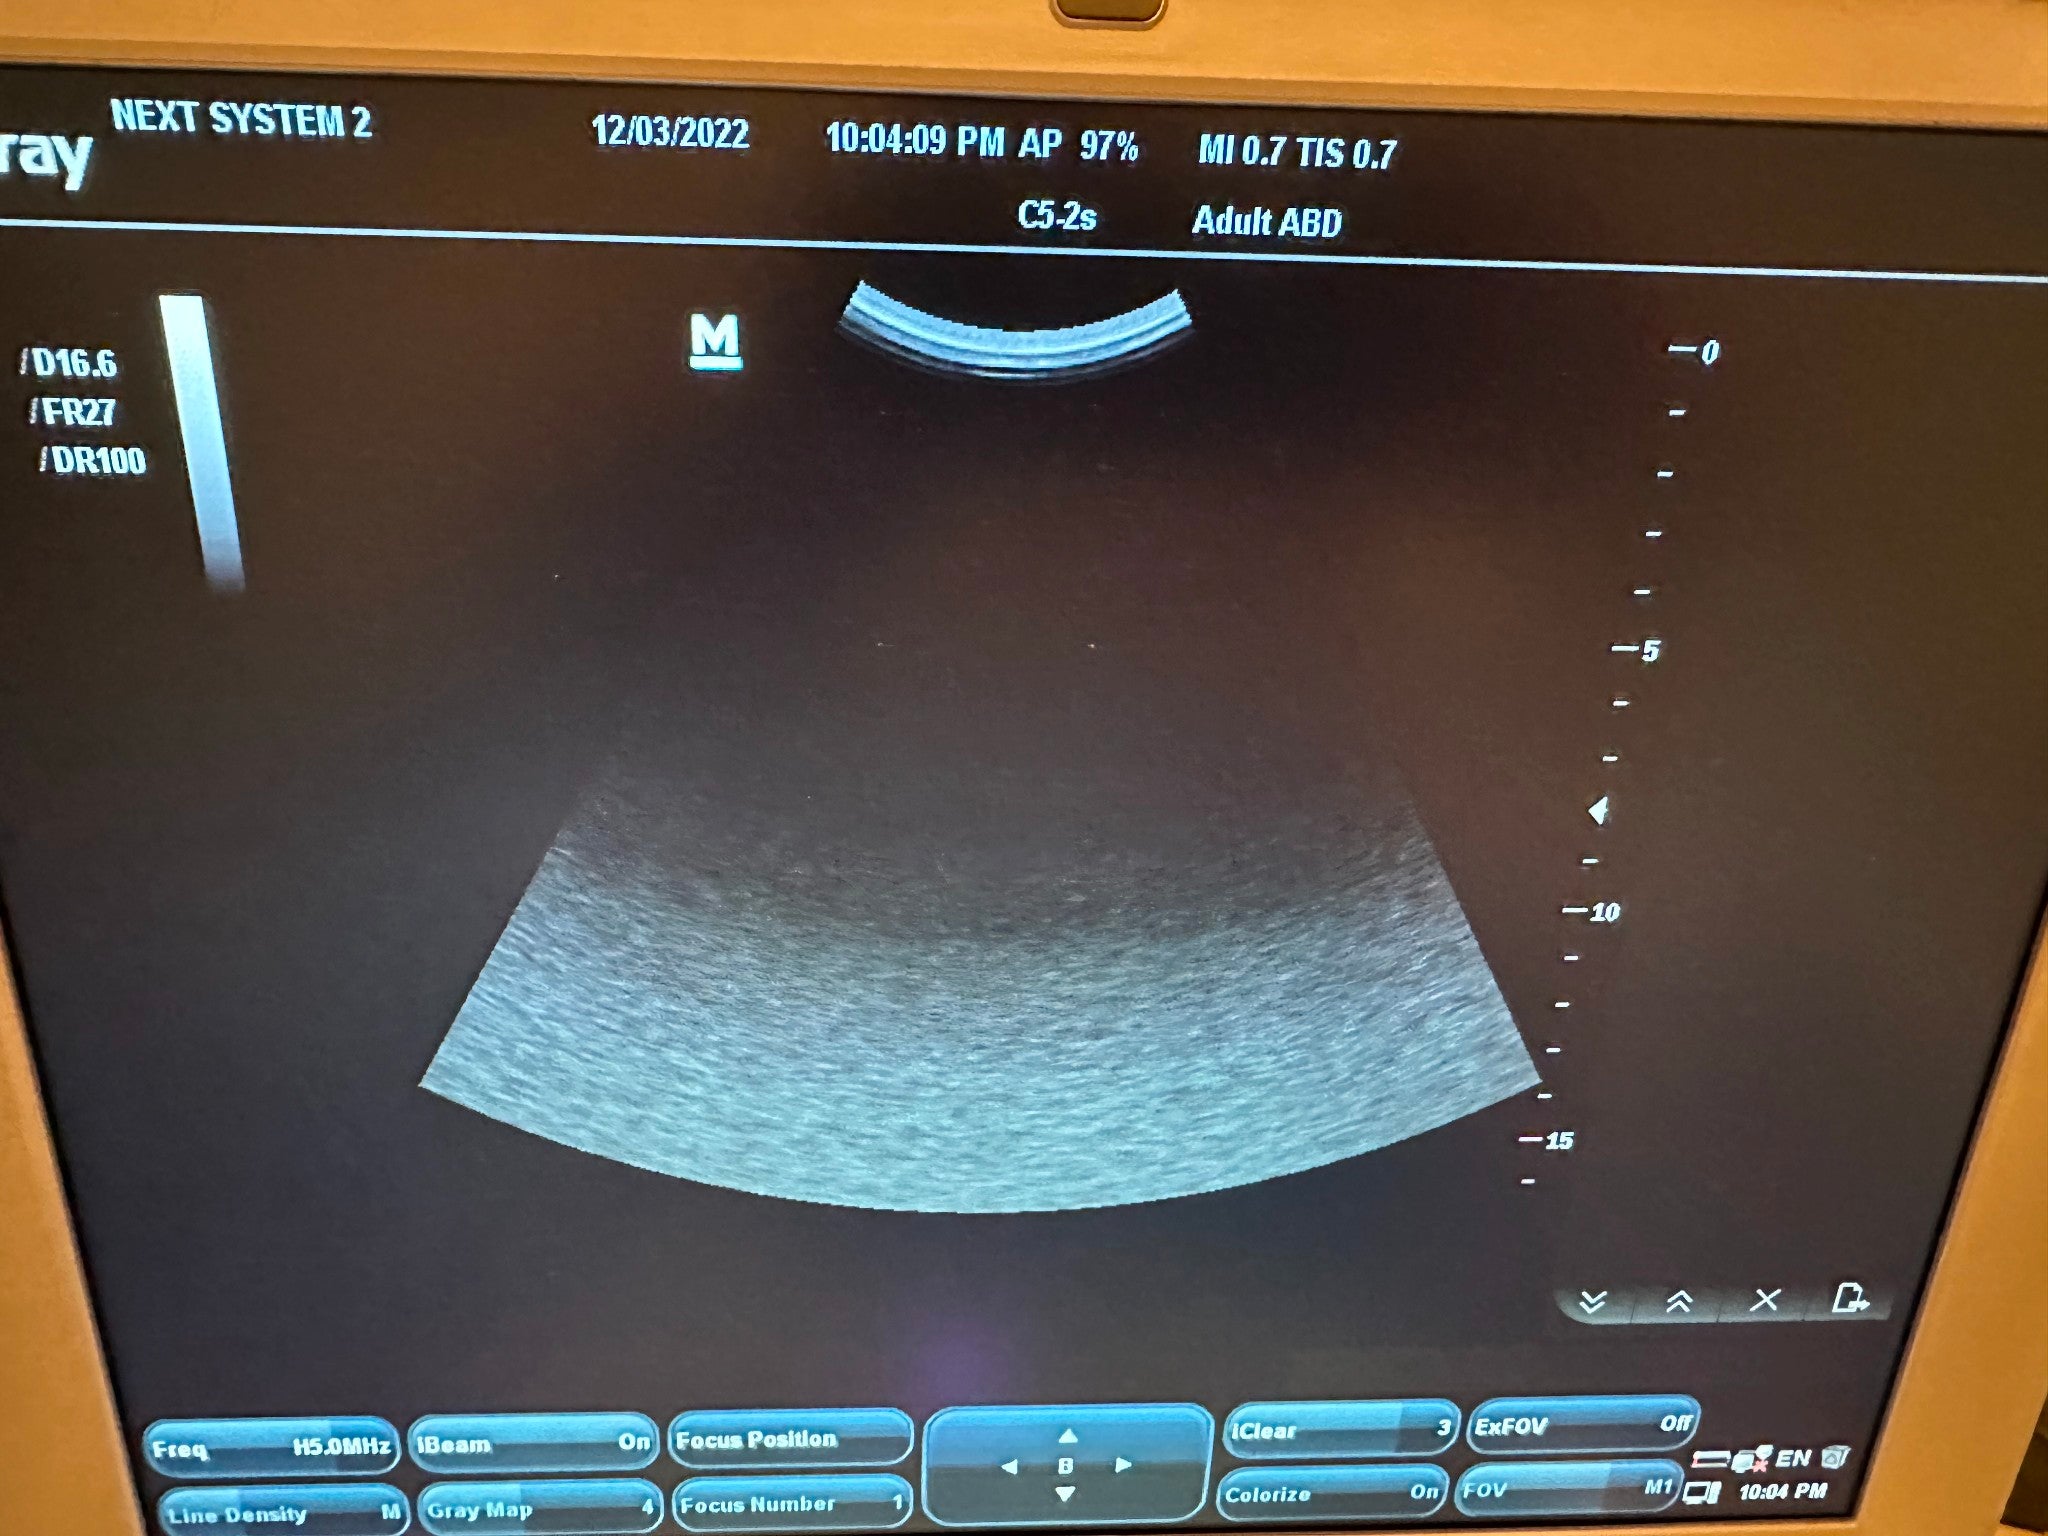

DIAGNOSTIC ULTRASOUND MACHINES FOR SALE

Toshiba PVT-575MV Ultrasound Volumetric 4D Probe

Sale price$ 4,738.20